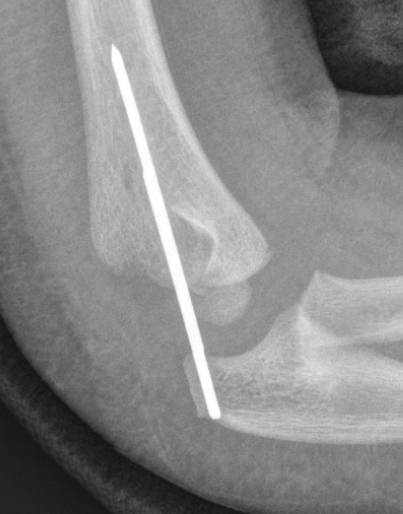

Arthrogram

Closed reduction

Closed reduction + percutaneous K wires

May need arthrogram to visualize distal humerus epiphysis